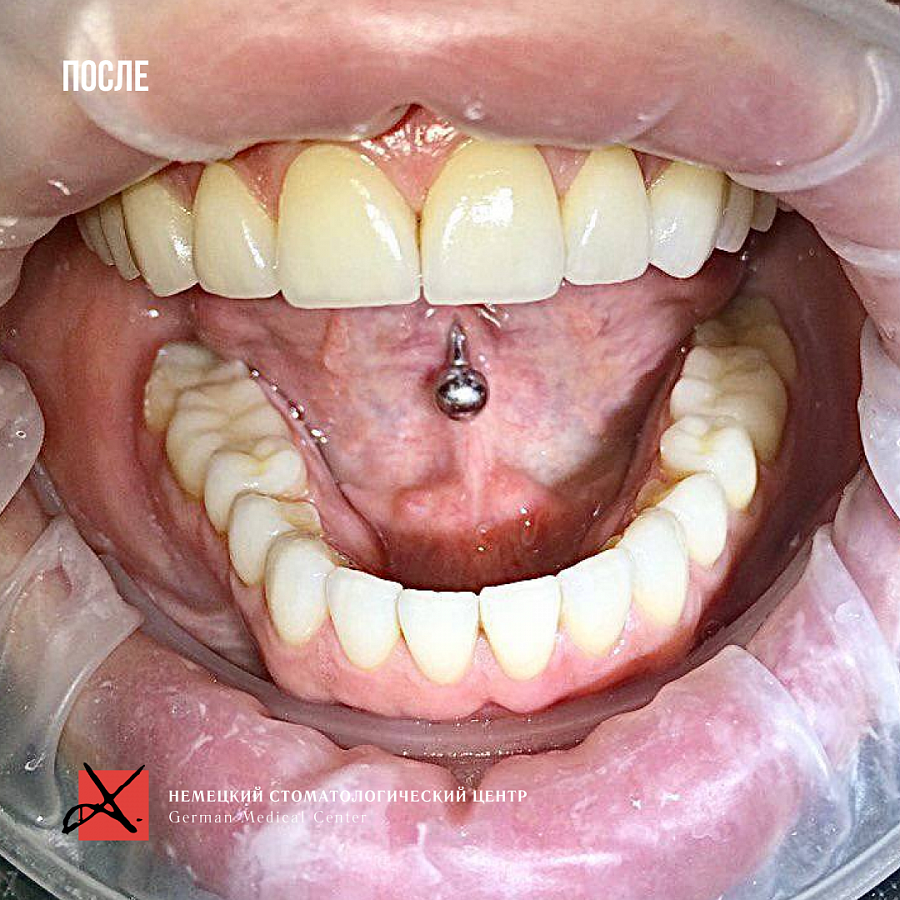

Провели санацию, сделали и установили красивые натуральные виниры.

Что получили?

Результат на фото говорит лучше всяких слов. Пациентка очень довольна результатом!

Результат лечения